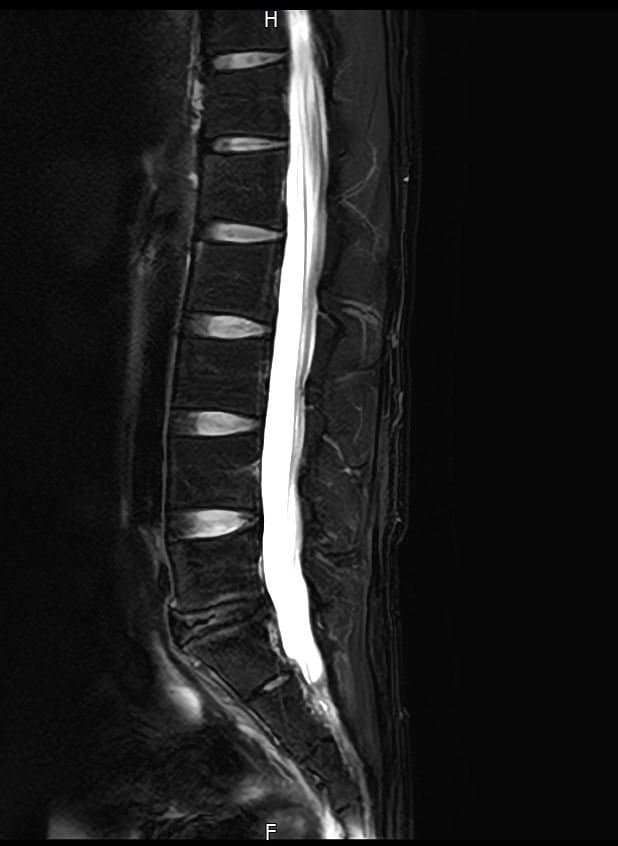

양쪽 엉덩이 염좌 6주째인데 mri 촬영한것좀 봐주세요

엉덩이 양쪽 염좌가 6주됨

방사통 없음 저림 없음 재채기 , 계단타기 전부 정상 , 숙일때 통증 없음

엉덩이 위쪽 바깥쪽 부분이 아픔 압통점 있음

177 / 66kg 약간의 퇴행성이 보인다는데 엉덩이 염좌와는 연관 없을꺼라고 하는데

영상과 증상을 종합해보면 전체적으로 척추배열은 양호하나, 요추4~5번과 요추5번~천추1번 사이의 디스크 수핵이 약간 검게 변한 퇴행성 변화가 관찰됩니다. 다만 신경을 심하게 압박하는 추간판탈출증 소견은 뚜렷하지 않습니다.현재 방사통이나 저림이 없고 특정부위에만 압통이 있다면 의료진의 소견대로 허리디스크보다는 근육 몇 인대문제일 가능성이 높습니다.말씀하신 부위는 염좌로 인해 예민해진 근막이나 인대가 완전히회복되지 않아 컨디션에 따라 통증이 반복될수 있습니다. 6주째 통증이 반복된다면 단순 휴식보다는 물리치료나 도수치료를 통해 굳어있는 근막을 풀어주는 것이 회복에 도움이 됩니다. 빠른쾌유를 빕니다!

MRI 영상상 관절 주변 조직의 부종이나 구체적인 염증 부위를 세밀하게 확인하는 과정이 꼭 필요해 보입니다.